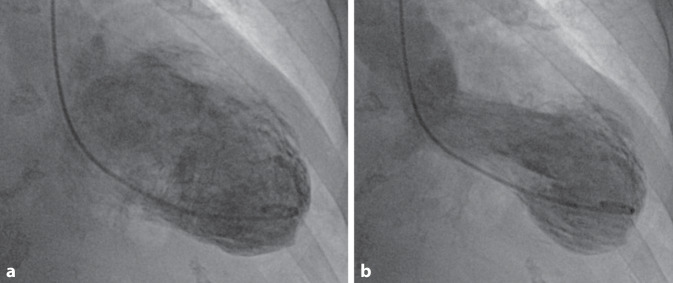

Die linksventrikuläre Funktion ist eine wesentliche prognostische Determinante des kardial kranken Patienten. Eine echokardiographische Untersuchung sollte nach Möglichkeit vor der invasiven Linksherzkatheteruntersuchung erfolgen (I, C). Hiermit lassen sich viele Fragestellungen (linksventrikuläre Funktion, Klappenvitien etc.) im Vorfeld klären, und somit kann auf eine Lävokardiographie in den meisten Fällen verzichtet werden (s. Beispiel in Abb. 11). Sollte eine angiographische Darstellung des linken Ventrikels durchgeführt werden, so sollte diese mindestens in einer RAO-Projektion (30°), ggf. zusätzlich in LAO (60° oder 45°) erfolgen (ggf. Abweichung der Projektionen bei spezifischen Fragestellungen, z. B. LAO ggf. lateraler oder kranialer bei Mitralinsuffizienz). Eine simultane biplane Darstellung ist wegen der Kontrastmittelersparnis zu bevorzugen. Der Katheter sollte möglichst extrasystolenfrei in der Mitte des linken Ventrikels, entfernt von der Mitralklappe platziert werden. Bei volumenbelastenden Vitien, besonders bei Mitralinsuffizienz, ist ein erhöhtes Injektionsvolumen erforderlich. Die Passage der Aortenklappe und KM-Injektion sollten mit einem Pigtail-Katheter erfolgen, da dies das Risiko einer Dissektion reduziert. Bei Aortenklappenstenose kann die Passage der Klappe mit einem AL-/ bzw. JR-Katheter und einem geraden Draht erfolgen.

Für rechtsventrikuläre Biopsien sollte die favorisierte Entnahmestelle das interventrikuläre Septum (IVS) sein. Bei linksventrikulären Biopsien ist die laterale/posterolaterale Wand des Ventrikels retrograd über die Aortenklappe aufzusuchen. Zwei angiographische Beispiele für Myokardbiopsien sind in Abb. 12 dargestellt.